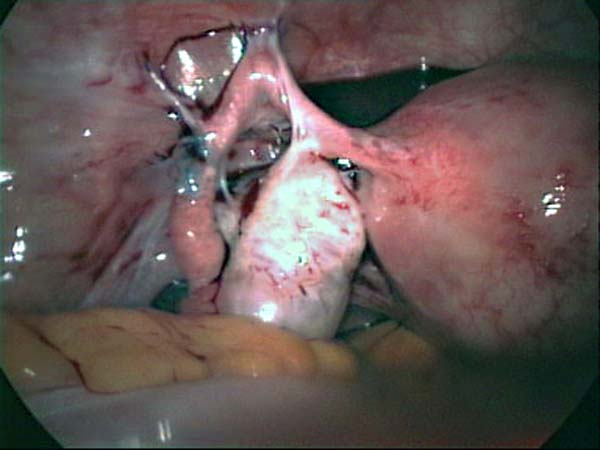

Laparoscopy Photos Ovarian Cyst Ovarian Cystectomy Uterine Septum Tubal Pregnancy